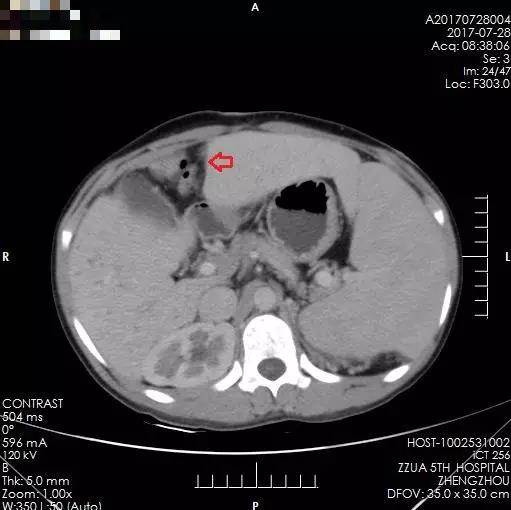

术后3年,未见肿瘤复发,腹腔内静脉曲张程度较前减轻。

术后3年,箭头所示为多发肝内胆管囊样扩张较前无明显变化

之后的两年里,小夏定期来院复查,肝脏内无肿瘤复发表现,病情平稳。然而,虽然解决了肝脏内肿瘤问题,但小夏的肝脏存在先天性胆管扩张、肝硬化及门静脉高压,食管下段、胃底及腹腔内有明显的静脉曲张,门静脉高压仍然缓慢进展,两年后因上消化道出血再次来到郑州大学五附院。完善相关检查,肝内未见肿瘤复发迹象,但门静脉高压症状明显,为预防再次消化道出血,缓解门静脉高压,经全面术前评估,小夏于2016年8月接受了全麻下行食管下段、胃底贲门周围血管离断术、脾动脉结扎、脾肺分流术。手术顺利完成,术后恢复良好,无任何并发症,术后定期复查,肝内未见肿瘤复发表现,门静脉高压有所缓解,病情平稳,小夏未再出现呕血。